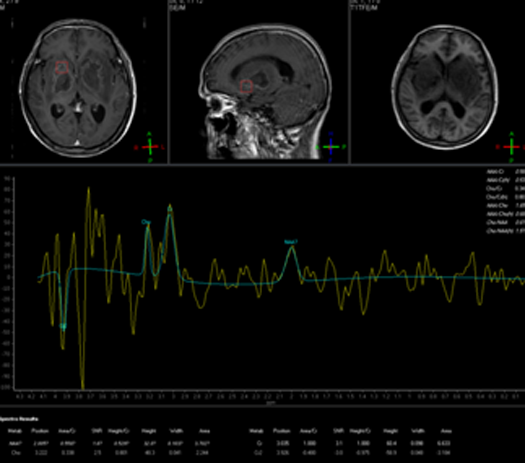

影像资料:

2015-11-27MR:双侧基底节区及双侧大脑脚示较对称片状异常信号, T1WI呈不匀低信号影,T2WI呈不匀高信号影,FLAIR序列呈不匀高信号,累及视交叉、视束及部分丘脑。2015-12-04复查:双侧基底节区及双侧大脑脚病灶范围较前稍增大。2015-12-07增强后病变呈多发环形薄壁或片状强化,DWI呈不均匀高信号。右侧基底节区病灶感兴趣区,可见Cho峰、NAA峰及Cr峰,Cho峰未见明显升高,Cho/Cr比值约为0.34,NAA/Cr比值约为0.56,Cho/NAA比值约0.61。综合平扫、增强、DWI、MRS所见,可排除肿瘤性病变,支持感染性病变(真菌或病毒感染可能性大)。